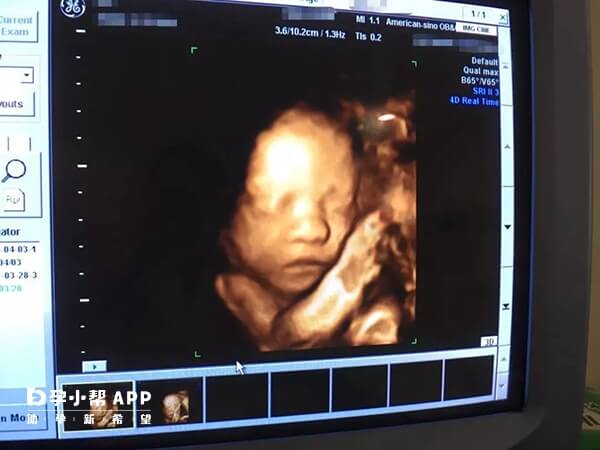

四维彩超qualhigh1的真正含义其实是表示超声质量、设备品质,1代表的就是一等质量。很多网友们都会拿四维彩超数据看男女,说qualhigh1就是生女宝的意思,但大家要知道我国是禁止医学性别鉴定的,医院绝不可能会将性别信息暗示在报告上,所以不要被谣言所误导。如果大家稍微注意以下,其实就会发现很多超声检查项目报告单图像上都会有qualhigh1、qualhigh2的字样,他并没有什么特殊的含义,只是单纯的成像质量而已。

Qualhigh1实际上是在四维彩超时会显示的数据,它表明的是对在做四维彩超检查,所使用检查设备的等级显示,不同的等级设置检查不同的疾病,检查不同的形式。因为四维彩超对于专业性的要求是很高的,每个人的身体情况都不一样,医生会根据每个人的具体情况来随时调节仪器,就会出现Qualhigh1的标志。

准妈妈拿到四维彩超报告单多数会一脸茫然,除了一些专业的医学名词外,还会有很多字母,很多都看不懂,下面就为大家解读四维彩超单上字母的含义。